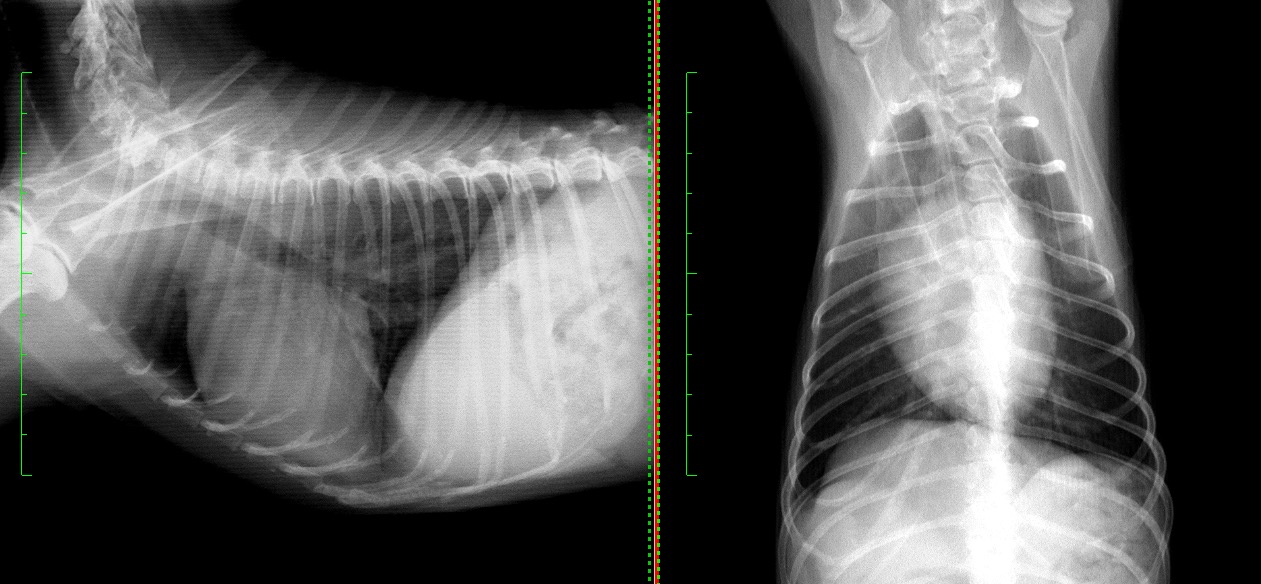

退院1週間後の再診時の胸部X線では肺野の不透過性も完全に改善し、呼吸状態はもちろん、元気や食欲などの一般状態も全く問題ない状態でした。